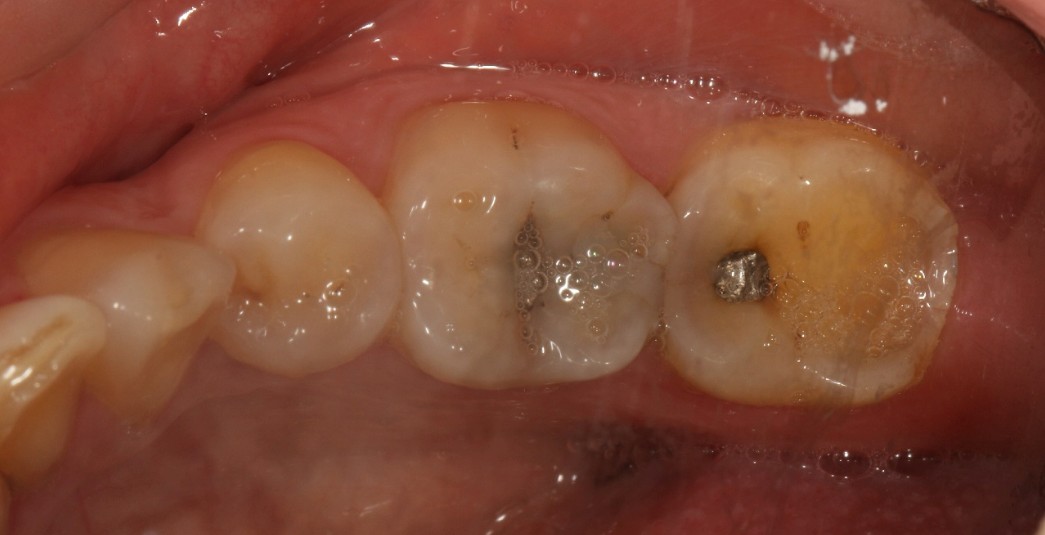

口腔检查时,会经常遇到以前补的银汞合金边缘变色,探有卡顿,形成了继发龋坏,建议重新充填或者瓷嵌体修复;瓷嵌体修复技术,可以非常好的恢复牙体形态和非常密合的边缘,色泽也非常逼真;我们采用CEREC(德国瓷睿刻)椅旁加工技术,达到最佳修复效果!